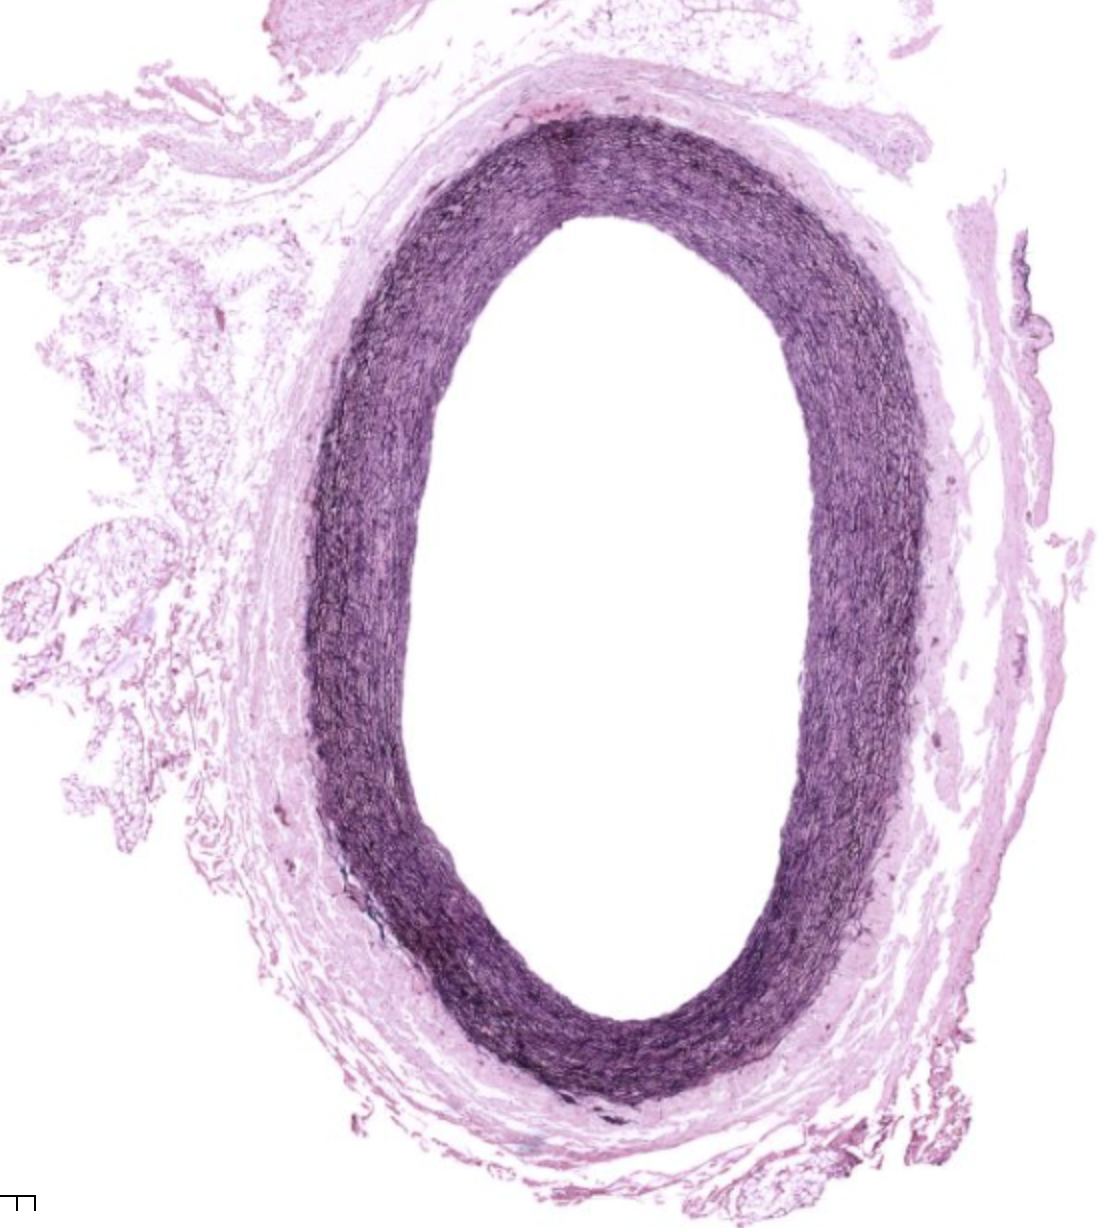

Elastic Arteries

Notable features:

found in areas of high blood flow (aorta, pulmonary artery)

In the aorta, tunica media is thick and has lots of elastic fibers

Vaso Vasorum: special group BV that provide nutrition to walls of arteries (small BV in tunica adventitia)

Aorta, elastic artery

3 Layers:

Tunica intima (inner layer) SS endo lining

Tunica Media (eosinophilic)

Elastic lamellae (diffusion can work through them)

Nuclei in between lamellae (modified smooth muscle cells, secrete ECM)

Tunica adventitia (mostly CT)

IEL = internal elastic lamellae